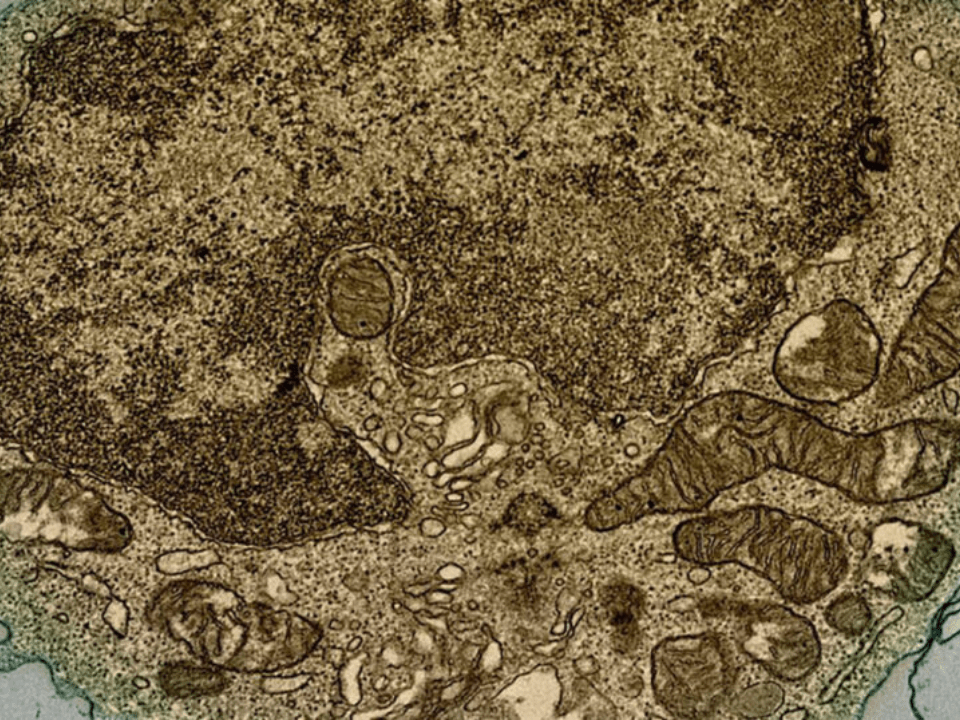

A pesquisa constatou que os camundongos que não expressavam o adaptador MyD88 em seus respectivos linfócitos B eram suscetíveis ao desafio experimental com o vírus Oropouche. “Observamos que eles apresentavam menor quantidade de anticorpos específicos e menor avidez ao vírus que camundongos normais (selvagens) no teste Elisa, que faz sua quantificação, além de menores títulos de anticorpos neutralizantes ao vírus, medidos por teste de neutralização de redução de foco”, relata o professor. “Os camundongos suscetíveis à infecção viral apresentavam menor número de células secretoras de anticorpos no baço, como plasmablastos, e células B de zona marginal que podem se diferenciar em produtoras de anticorpos também, sendo essa avaliação realizada por teste de citometria de fluxo.”

O professor enfatiza que também foi identificada uma subpopulação de células produtoras de anticorpos derivada de linfócitos B da zona marginal do baço. “Ela consegue produzir anticorpos protetores rapidamente no início da infecção e de forma suficiente para evitar a morte por encefalite dos animais testados”, descreve. “Uma das descobertas mais importantes desse trabalho é que o tratamento baseado na infusão de amostras de soro de camundongos imunes ao Oropouche, com anticorpos neutralizantes, restringiu a replicação viral e evolução do quadro para doença grave, quando administrados nos primeiros dias após a infecção em animais suscetíveis ao vírus.”